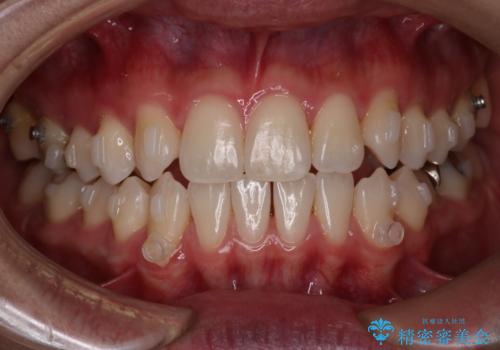

- 右上2番が欠損しており、歯並びをバランスよくしたいということで来院されました。

ワイヤー装置とマウスピースで悩まれていましたが、マウスピースで治療可能と判断致しましたのでマウスピースにて治療しました。

IPR、歯列弓拡大、ゴム掛けを行い歯並びを整える治療計画を立てました。

右上2番が欠損しているため、見た目と噛み合わせの両方のバランスを整えるために経過を追いながら必要な部位にゴム掛けをしました。

最終的に、見た目も噛み合わせも患者様に満足いただけました。